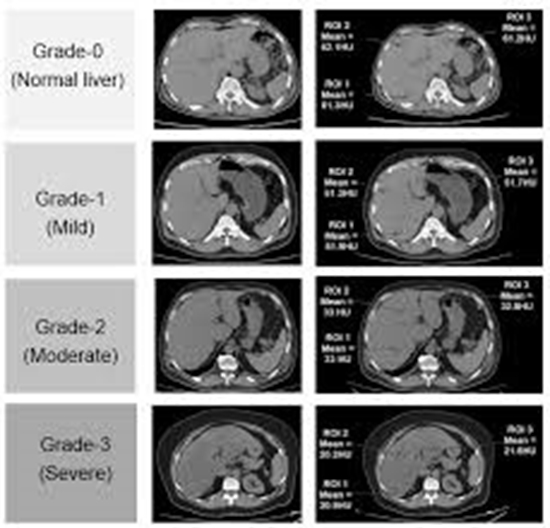

بررسی دقت تشخیصی سی تی اسکن با کنتراست در تشخیص و grading کبد چرب در مقایسه با نمونه های پاتولوژی بیمارانی که طی سال های96 تا 99 در بیمارستان امام خمینی تحت عمل جراحی هپاتکتومی قرار گرفته اند

دقت تشخیصی سی تی اسکن با کنتراست در تشخیص و grading کبد چرب